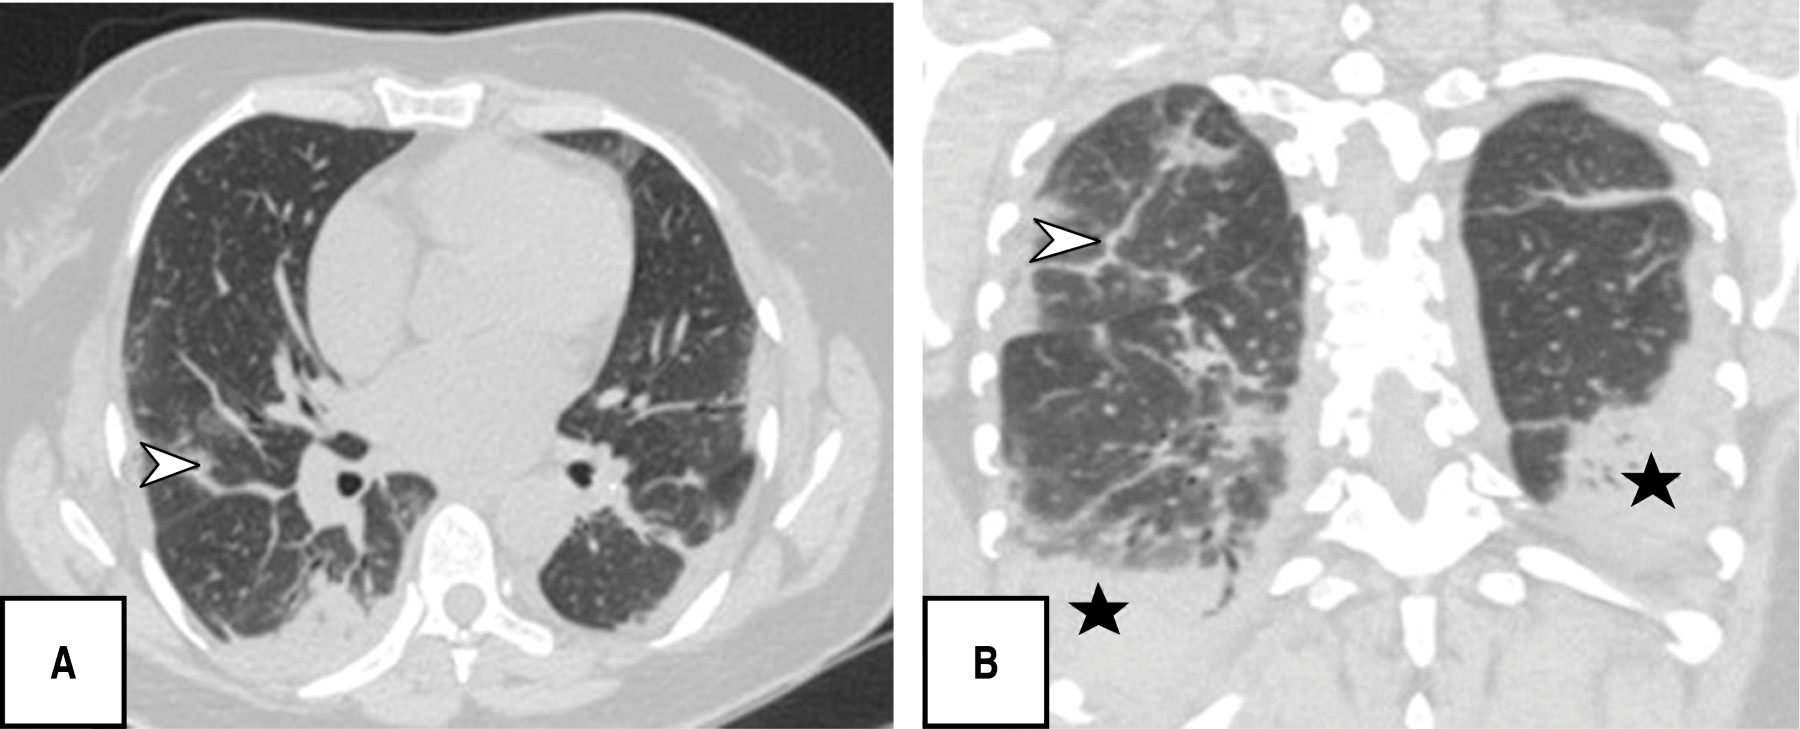

Durante la evaluación tomográfica se obtuvo que los patrones pulmonares más frecuentes fueron: patrón en empedrado (120 [80.5%]), bandas pleuroparenquimales (118 [79.2%]) y patrón en vidrio deslustrado (110 [73.8%]), patrón reticular 82 [55%]), y en menor porcentaje dilatación vascular (56 [37.6%]) y patrón consolidado (52 [34.9%]) (Figuras 1, 2, 3 y 4).

En cada paciente se detectó que tenía afectados cinco de cinco lóbulos pulmonares, 144 (96.6%), con un porcentaje total de afectación de 26-49%, (96 [62.4%]); la distribución de afectación pulmonar más característica fue central y periférica (86 [57.7%]), y sin predominio de segmentos (86/57.7%) seguida de la localización en segmentos posteriores (59/39.6%), todas con significancia estadística (p < 0.05). El puntaje de severidad PATPAS que presentaron los pacientes fue moderada (93 de 149 pacientes [62.4%]).

Es de resaltar que la mayoría de los pacientes en esta investigación se presentaron en una fase crónica/avanzada de la enfermedad encontrando como patrones predominantes el empedrado (120/149; 80.5%), bandas pleuroparenquimales (118/149; 79.5%) y en tercer lugar patrón en vidrio deslustrado (110/149; 73.8%), sin identificar ningún caso con hallazgos de atolón, neumotórax o árbol en gemación, otros estudios sí reportan como hallazgo predominante las opacidades en vidrio deslustrado seguido del patrón en consolidación y al respecto el derrame pleural, derrame pericárdico, linfadenopatía, cavitación, el halo reverso o signo del atolón y neumotórax son poco frecuentes, pero pueden observarse con la progresión de la enfermedad.19-21

Soriano et al. reportaron que la presencia de opacidades en vidrio deslustrado, el patrón reticular, el patrón en empedrado, las líneas subpleurales, el engrosamiento pleural y la fibrosis se encontraron con mayor frecuencia en la fase intermedia/progresiva, especialmente en la fase avanzada; de forma similar observamos una correlación significativa (índice de Pearson de 0.65) entre el patrón predominante y la fase evolutiva de la enfermedad.23 Los puntajes de la TC del grupo de etapa progresiva fueron significativamente mayores que los del grupo de etapa temprana; sin embargo, en este estudio no hubo significancia estadística entre en patrón de TC y el puntaje de severidad.